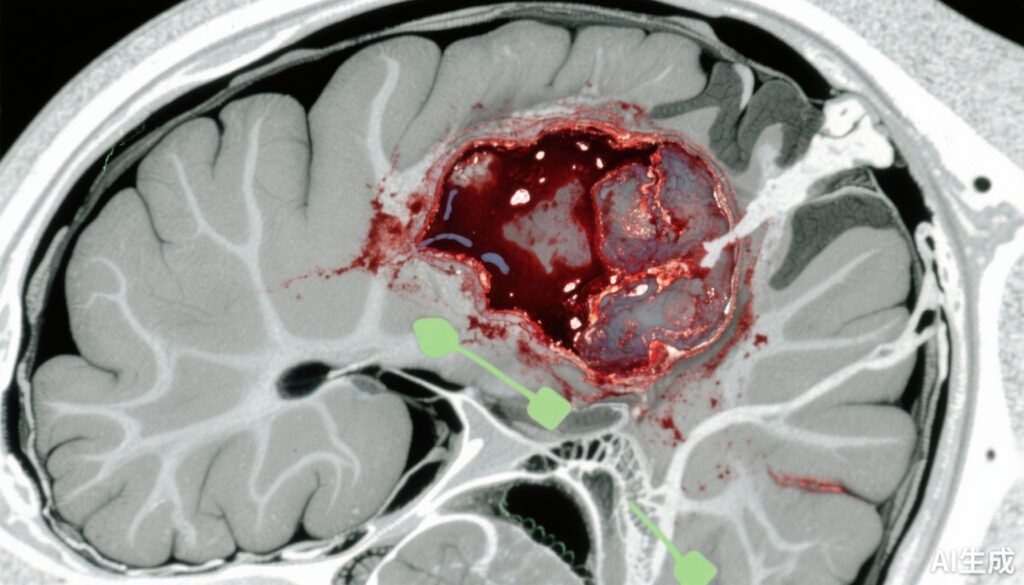

Traumatic brain injury (TBI) remains a major cause of morbidity and mortality worldwide, with acute subdural hematoma (ASDH) representing one of the most critical intracranial lesions. ASDH results from bleeding between the dura mater and the brain surface, often due to head trauma, leading to increased intracranial pressure and potential herniation. Traditional management involves emergent surgical evacuation to reduce mass effect and secondary brain injury. However, the heterogeneity of injury severity and patient factors has left uncertainty whether immediate surgery confers superior outcomes compared to conservative treatment in many cases. This uncertainty generates variability in clinical practice and highlights an unmet medical need to clarify optimal treatment strategies that balance risks and benefits in ASDH management.

This comparative effectiveness study analyzed data from the prospective observational Transforming Research and Clinical Knowledge in Traumatic Brain Injury (TRACK-TBI) Study, which enrolled patients from February 1, 2014, to July 31, 2018. The setting comprised 18 Level 1 trauma centers across the United States. Inclusion criteria included patients with nonpenetrating TBI who presented to the emergency department and were admitted within 24 hours after injury with ASDH verified by acute head computed tomography (CT) scan.